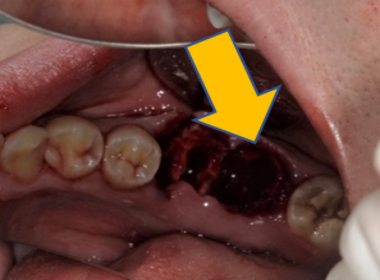

| 0114 #16 右上第一大臼齒 |

![]() |